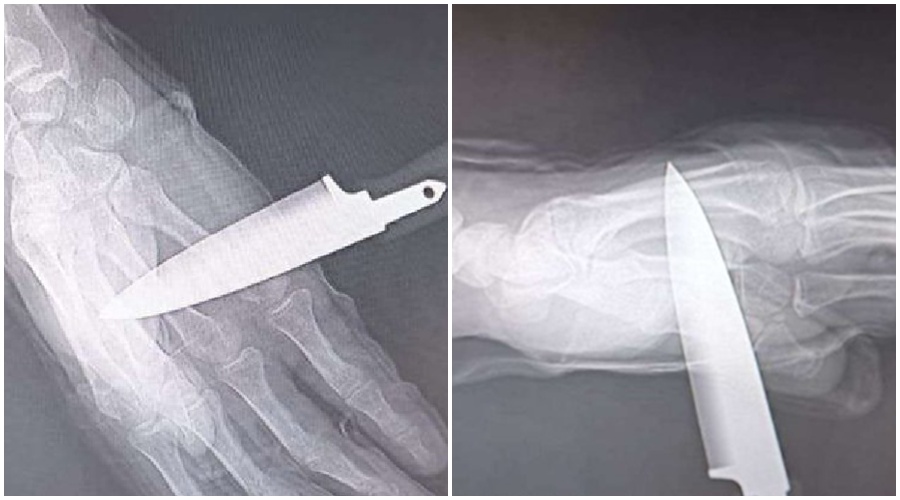

Un agente de la Policía Nacional ha resultado herido por arma blanca durante una intervención en un domicilio de Baza tras una disputa familiar entre madre e hijo. El agresor, que ocultaba un cuchillo, le asestó una puñalada en el pecho —frenada por el chaleco— y otra que le atravesó la mano.